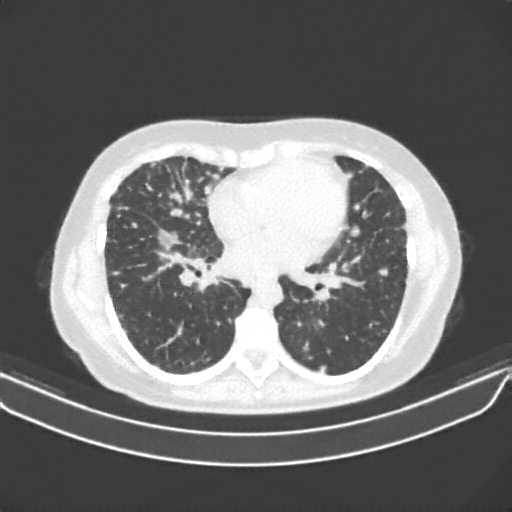

Original NATIVE CT scan (input)

Full window (WL 1023.5, WW 4095 β†’ Low βˆ’1024, High +3071)

Lung window (WL -600, WW 1500 β†’ Low βˆ’1350, High +150)

Mediastinum window (WL 40, WW 400 β†’ Low βˆ’160, High +240)